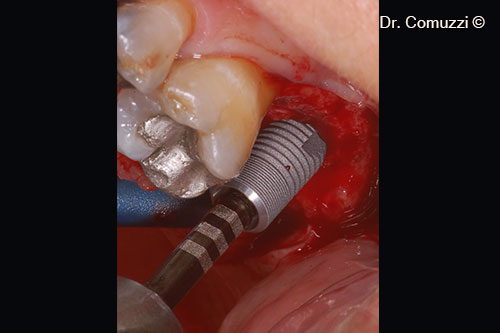

4. Implant insertion (Astra, 9-mm length and 5-mm diameter)